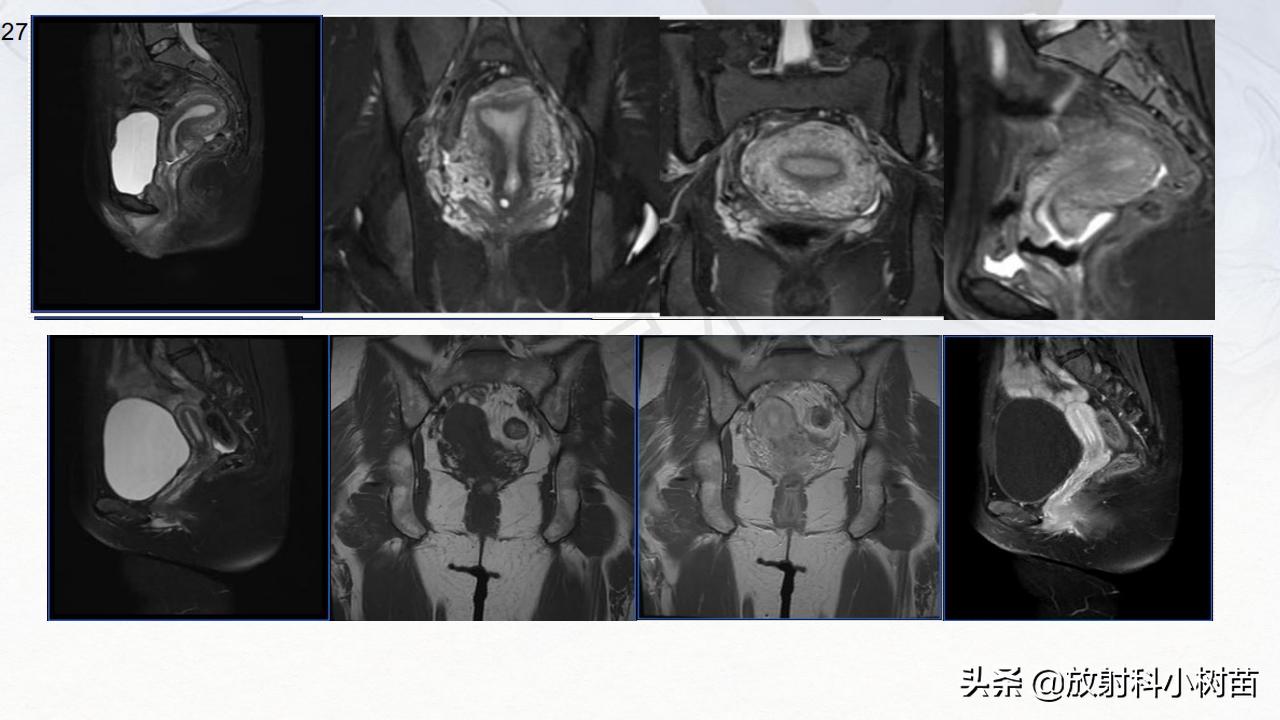

子宫体:肌层?(腺肌症,肌瘤,肉瘤),内膜?(增生,息肉、内膜癌)

宫颈:(息肉,囊肿,肌瘤,内膜癌)